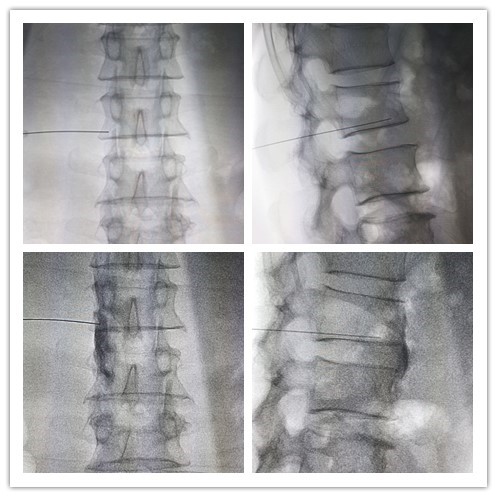

61 10 2 DSA 40

1988 9 C CT